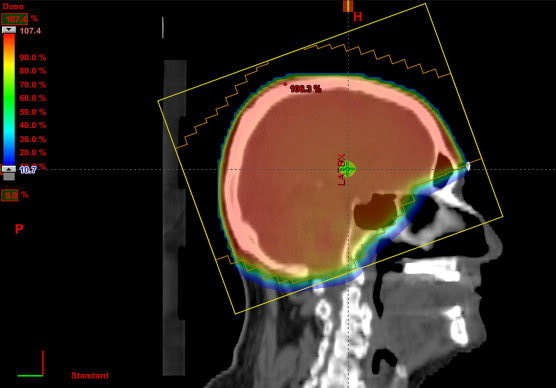

-الاعراض المصاحبه لانتشار الورم في الدماغ